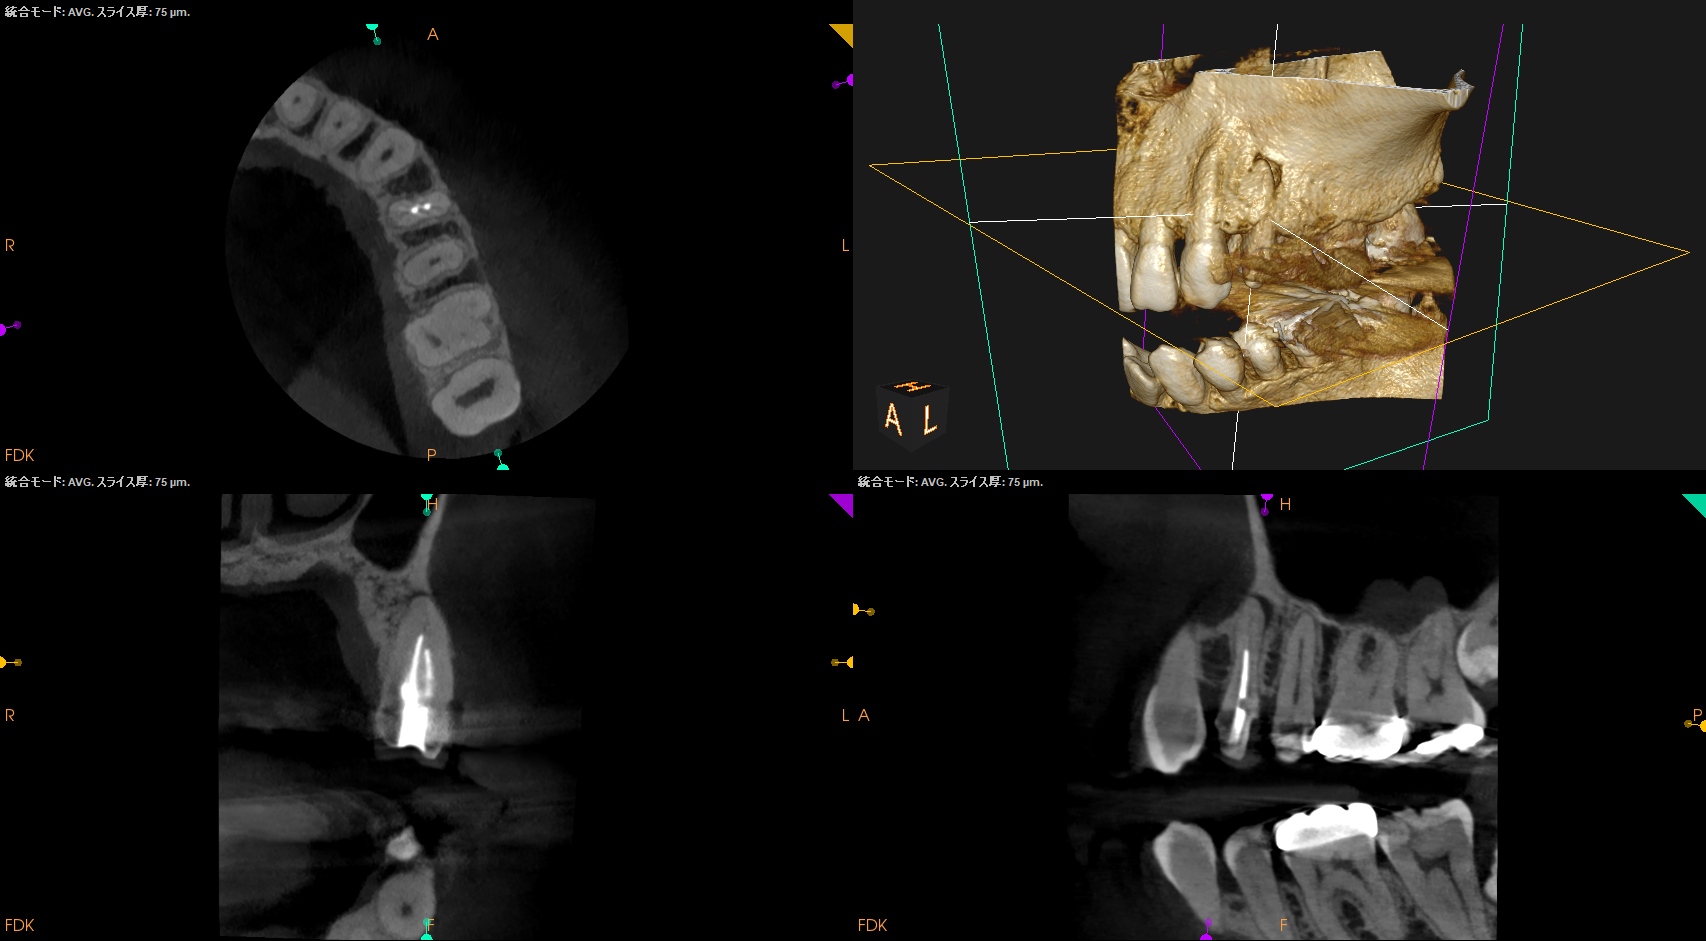

ということは、治療方法はApicoectomy一択だ。

その際は、

それほど難しいApicoectomyではない、とわかる。

CBCTを分析すれば、だ。

#12 Apicoectomy(2025.3.7)

Apexの位置のOsteotomyすると、そのApexは容易に発見できた。

根尖を3mm切断し、メチレンブルーで染色した。

問題はない。

逆根管形成し、逆根管充填した。

ペントロンジャパンの

エンドセム MTA クイックペースト R

で逆根管充填した。

いわゆるシーラー逆根管充填(そんな言葉があるのか?)である。

術後にPA, CBCTを撮影した。

#12 Apicoectomy 1yr recall(2026.2.27)

1年前と比較した。

問題は解決した。